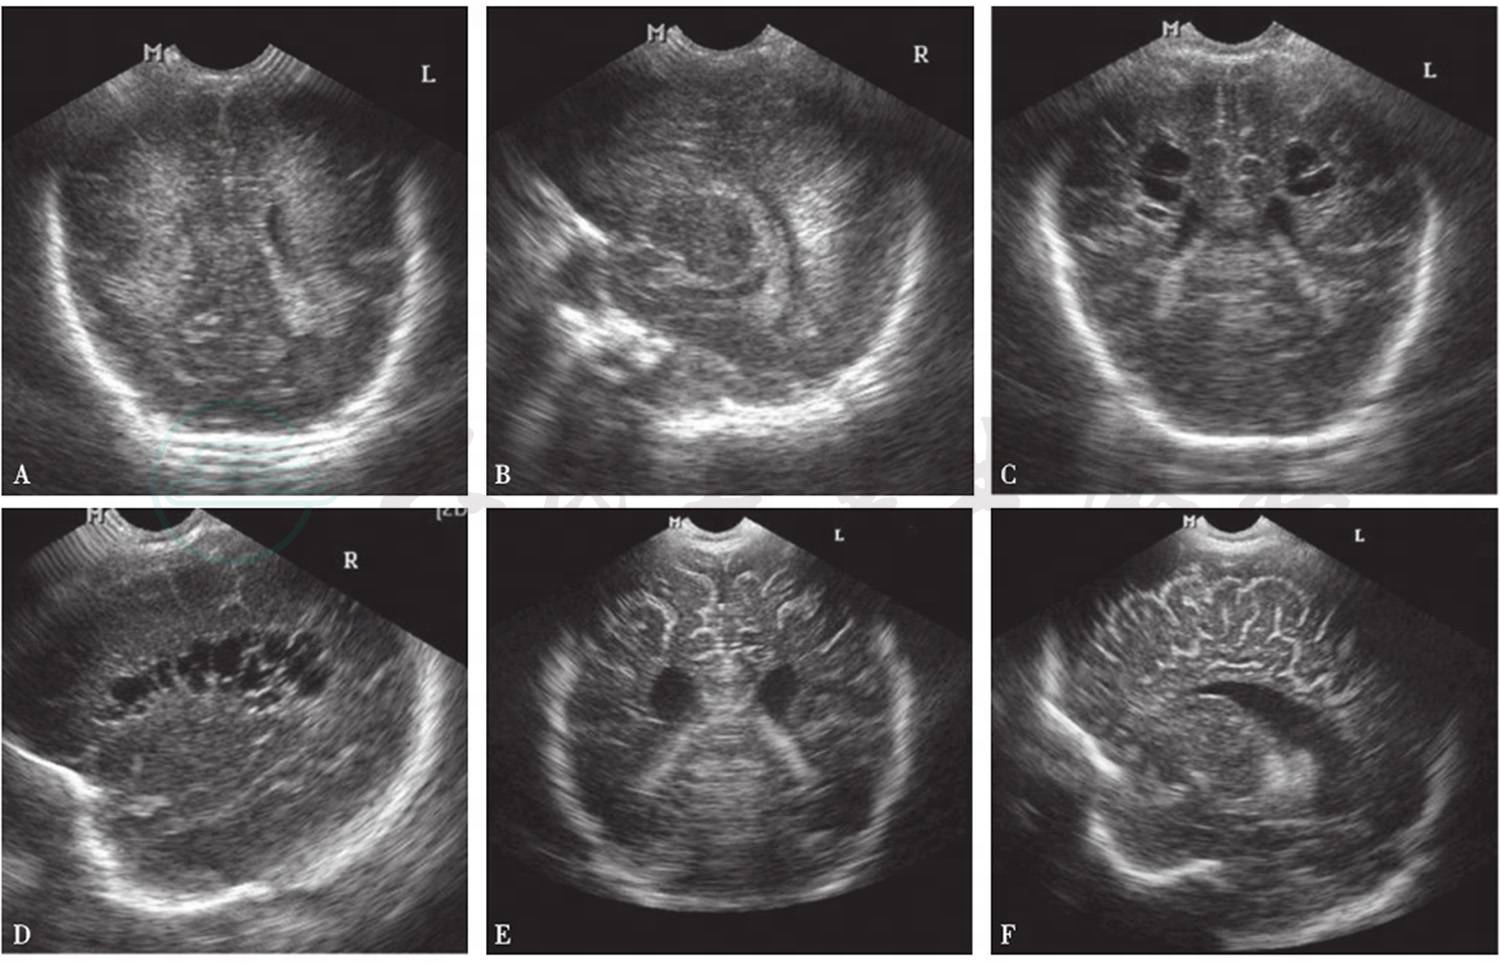

1)早期

损伤部位回声增强,冠状面扫描可见异常回声分布于侧脑室角的外部和侧脑室旁。在旁矢状面扫描,分布于脑室上方和侧脑室后角三角区附近。

2)PVL形成期

3~4周后软化灶逐渐出现,在上述部位,部分异常回声转化为多个无回声小囊腔,有些可融合成较大囊腔。

3)后期

1~3个月后,一些小囊在影像上消失,脑室增宽(图2)。

图2脑白质损伤的超声影像

A、B.损伤早期,脑室旁白质回声增强;C、D. PVL形成期;E、F.损伤后期,侧脑室增宽

引自:实用新生儿学.第5版.ISBN:978-7-117-27403-6.主编: